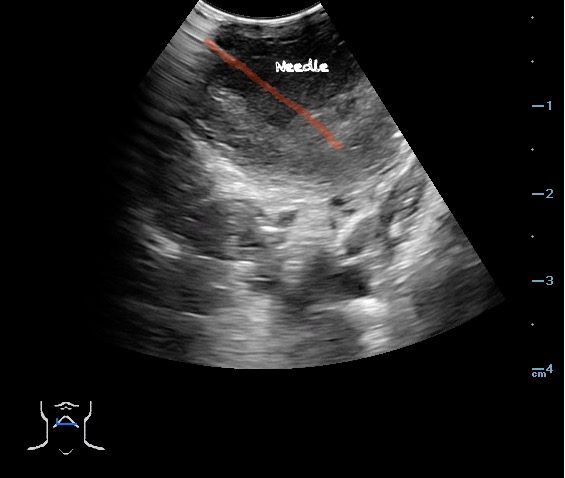

- Peritonsillar abscess is visualized as a hypoechoic or complex cystic structure

- Ultrasound-guided needle aspiration of a PTA:

- The depth of the abscess cavity from the mucosal surface should be noted to determine the length of the needle required to drain the abscess.

- Figure 45. and 46. PTA aspiration

- The carotid artery is seen as an anechoic tubular structure along the posterolateral aspect of the tonsil on ultrasound. Its relationship to the abscess cavity should be determined. Color Doppler can help locate the carotid artery.

- The ability to simultaneously image and introduce the needle allows the emergency physician to track the entire course of needle and prevent complications such as puncturing the carotid artery.30-32

- Use Color Doppler to determine the relationship of the carotid artery to the abscess cavity prior to performing aspiration.